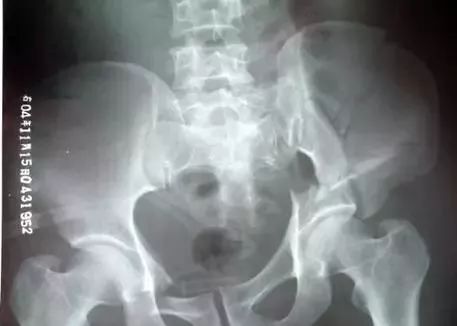

3.、Malgaigne骨折(玛尔盖涅骨折)

指存在垂直旋转不稳的纵向骨盆骨折,骨盆后环有骶髂关节脱位或髂骶骨的纵向骨折,骨盆前环可累计双侧耻坐骨支、耻骨联合等,常合并尿道损伤,需手术治疗。该骨折首先由法国医生Malgaigne描述,故此得名。

4、Straddle骨折(骑跨损伤)

指累积双侧耻骨上下支或双侧耻坐骨支的骨折,常合并尿道损伤,有时骨盆后环也受到波及,常规行CT检查。

5、Walther骨折(沃特骨折)

同时波及耻骨支及骶髂关节的髋臼骨折,且存在髋臼的内侧面向内移位,是骨盆骨折较严重类型,骨盆前后环稳定性均受到破坏,常合并休克,手术时需前后联合入路。